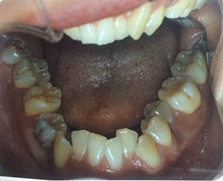

骨格性の問題が大きい歯並び(上顎) 骨格性の問題が大きい歯並び(下顎)

骨格性の問題が大きいので、当クリニックで矯正治療する場合は、 外科矯正治療となります。費用は顎変形症の適応となりますので、保険適応となります。装置は歯の表側よりブラケットという装置を装着します。期間は3年前後は必要かと思います。上顎は配列する為に両側で1本づつの抜歯が必要となります。下顎の左側 は親知らずの抜歯が必要です。右側は小臼歯が埋伏してるとの事なので、牽引できる

場合は保存しますが、状況により抜歯が必要となります。